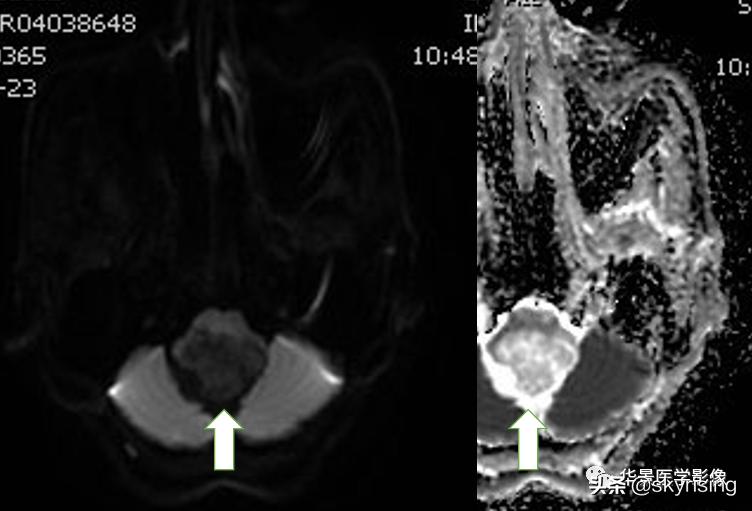

上图白色箭头:病灶呈DWI低信号,ADC高信号,信号欠均,提示弥散不受限。

小脑延髓池内见不规则异常信号影,呈长T1长T2信号,内部信号不均,边缘见稍粗大流空信号血管影,FLAIR少许片状低信号,增强呈明显强化,DWI不均质低信号,ADC不均质高信号。小脑半球、延髓、第四脑室受压变形。临近延髓变窄,呈长T1长T2信号。

总体以不规则实性占位病变,临近走行血管流空信号影,增强明显强化,DWI低信号为特点。